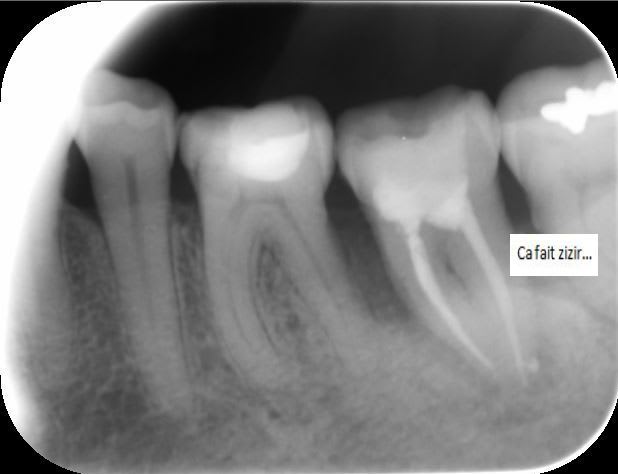

Lesion endo paro bdwn58 - Eugenol

J 0 obturation bof.. - Eugenol

J   3 mois  bonne surprise ya7tbg - Eugenol